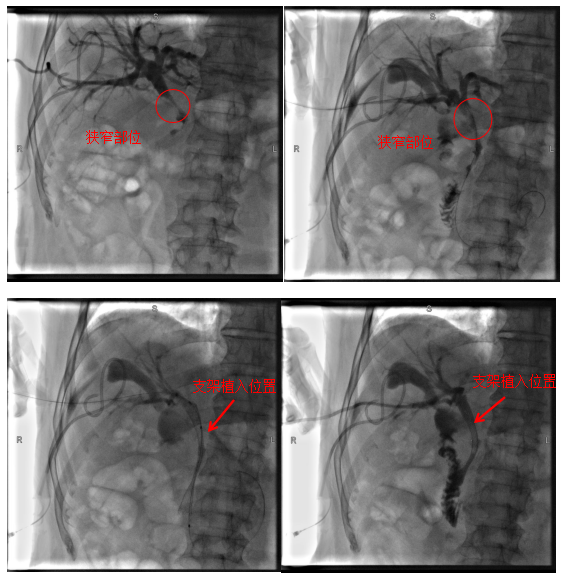

病例2

患者为72岁老年男性,因“右上腹疼痛2月,眼黄、尿黄1周”入院。入院后完善相关检查考虑胆管中段恶性肿瘤、梗阻性黄疸,患者心肺功能极差,心血管内科、呼吸与危重症医学科及麻醉科会诊评估后考虑患者无法耐受全身麻醉,肝胆胰外科团队充分评估后决定为患者行经皮经肝胆道支架植入术,手术顺利,术后患者黄疸逐渐消退,有效地改善了患者的生活质量,延长了患者的生存时间。

术中影像